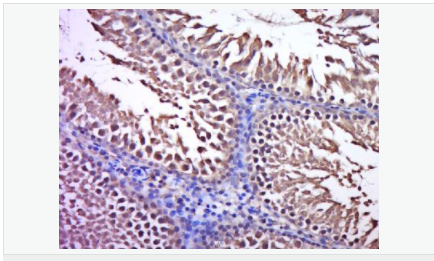

| 產品應用 | WB=1:500-2000 ELISA=1:5000-10000 IHC-P=1:100-500 IHC-F=1:100-500 ICC=1:100-500 IF=1:100-500 (石蠟切片需做抗原修復) not yet tested in other applications. optimal dilutions/concentrations should be determined by the end user. |

| 產品介紹 | C3orf32 (chromosome 3 open reading frame 32), also known as fls485, is a 353 amino acid protein encoded by a gene that maps to human chromosome 3p26.1. Chromosome 3 is made up of approximately 214 million bases encoding over 1,100 genes. Notably, there is a chemokine receptor gene cluster and a variety of human cancer related loci on chromosome 3. Particular regions of the chromosome 3 short arm are deleted in many types of cancer cells. Key tumor suppressing genes on chromosome 3 encode apoptosis mediator RASSF1, cell migration regulator HYAL1 and angiogenesis suppressor SEMA3B. Marfan Syndrome, porphyria, von Hippel-Lindau syndrome, osteogenesis imperfecta and Charcot-Marie-Tooth disease are a few of the numerous genetic diseases associated with chromosome 3. Subcellular Location: Cytoplasm. Tissue Specificity: Expressed in enterocytes of small and large intestinal mucosa (at protein level). Expressed in enterocytes, chromaffine and interstitial cells. SWISS: Q9Y2M2 Gene ID: 51066 Database links: Entrez Gene: 51066 Human SwissProt: Q9Y2M2 Human Unigene: 561182 Human Unigene: 740735 Human Important Note: This product as supplied is intended for research use only, not for use in human, therapeutic or diagnostic applications. |